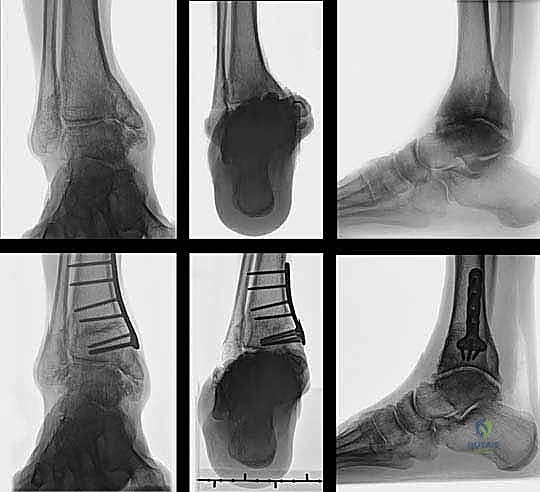

- الأشعة السينية أثناء الوقوف (Weight-Bearing X-rays): هذه هي الخطوة الأهم. لا يمكن تقييم تشوه الكاحل بدقة والمريض مستلقٍ. يجب أخذ صور أشعة طويلة للساقين بالكامل لتحديد "محور التحميل الميكانيكي" وقياس زوايا التشوه بدقة متناهية (مثل زاوية TAS وزاوية TLS).

- التثبيت الداخلي (Internal Fixation): بمجرد الوصول للزاوية المثالية، يتم تثبيت العظم في وضعه الجديد بقوة باستخدام شرائح معدنية متطورة (Locking Plates) ومسامير من التيتانيوم. هذا التثبيت القوي يضمن عدم تحرك العظم أثناء فترة الالتئام.

- إغلاق الجرح: بعد التأكد من التثبيت ووقف أي نزيف، يتم غسل المنطقة بمحاليل معقمة، ثم خياطة الأنسجة والجلد بطريقة تجميلية دقيقة لتقليل الندبات.

- وضع الجبيرة: يتم وضع جبيرة خلفية أو حذاء طبي واقٍ لحماية الكاحل وتثبيته في المرحلة الأولى من التعافي.